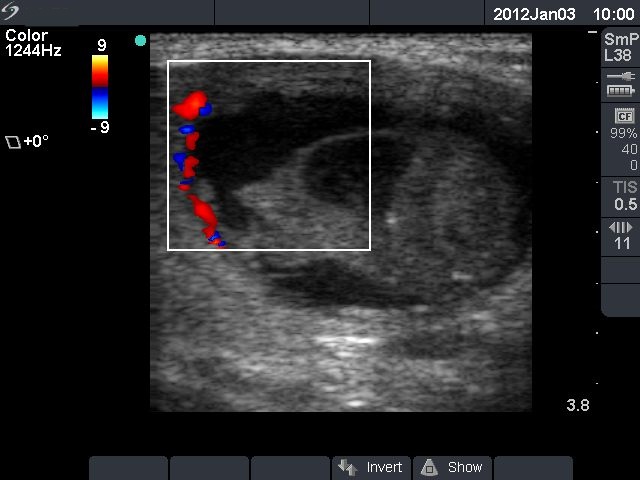

First row: ultrasonographic picture before sclerotherapy. The size of the lesion was 38x28x39 mm (width x depth x length).